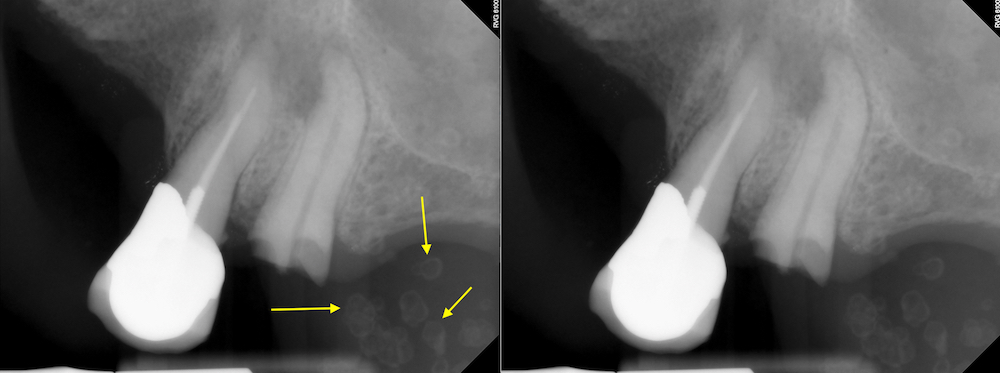

Доктор Сегаль. Удаление остеоидной остеомы.